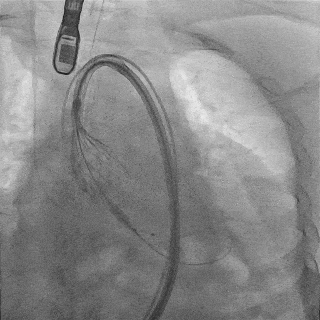

主动脉根部造影

TF29瓣膜,0位定位释放

瓣膜稳定释放至全展开

造影观察:瓣膜位置可,形态佳

左冠切线观察,瓣膜位置可

冠脉灌注良好

缓慢脱钩,瓣膜无位移

脱钩后造影

瓣膜位置可,无瓣周漏